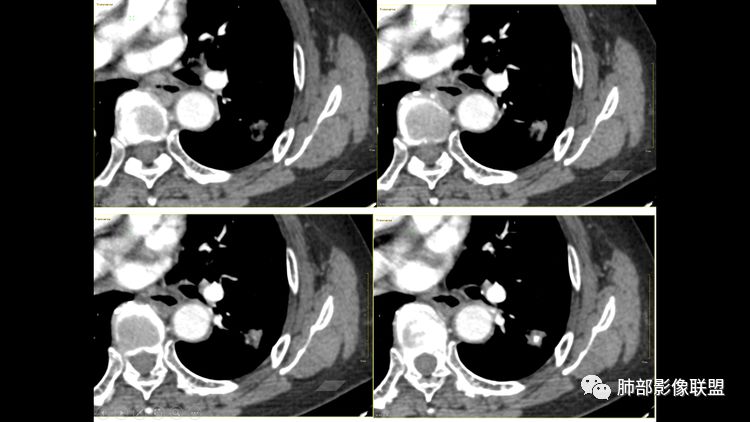

老年女性,气喘入院,发现左肺占位

睡神-阿豆豆:左肺下叶背段占位,边界尚清晰,有深分叶,有胸膜牵拉,有血管集束,支持恶性病变,不支持的如下,短毛刺不明显,病灶内有钙化。结核的话周围没有卫星灶。综合考虑肿瘤,鉴别结核。一切∮随缘:左肺结节,边缘光整,有分叶,轻度牵拉胸膜,形态规则,其内可见小片状钙化,增强后可见强化,病灶内似见小空泡,考虑:隐球菌,鉴别类癌蔡磊:左肺下叶占位,边缘较清,有深分叶,收缩牵拉线边缘光、清晰,内有钙化。与支气管关系不密切,增强后有强化,考虑恶性在前,错构、结核次选。M-Imaging :病灶边缘平直,其内斑片钙化,炎性肉芽肿,PC德芙~云味:左肺下叶占位,边缘较清GGO,有深分叶,边缘有膨隆有平直,胸膜牵拉,内有钙化。支气管近端有阻塞,有血管进入,增强后有强化,考虑恶性,待排隐球。丽:左肺下叶病变,边缘模糊不清,可见深分叶,内粗大钙化,轻度强化,不除外恶性可能飞鹰行动:左肺下叶病灶,有膨胀性表现,可见分叶征象,内部钙化位于一侧,见可疑小泡征,相邻叶间胸膜增厚,增强后可见血管穿入,其血管边缘毛糙,考虑恶性病变,腺癌,鉴别结核。巴伟:首先支持炎性红日东升:左肺下叶结节,边缘较光整、清晰,有分叶,外缘轻度牵拉胸膜,总体形态偏平直收缩,其内可见类圆形规则钙化(面积大于10%),增强轻度强化并见血管显影。考虑良性病变,炎性肉芽肿。平安是福:左肺下叶结节,轻度分叶,病灶内见钙化,血管穿行,中度均匀强化,边缘可见胸膜凹陷及平直,考虑结核,PC,鉴别诊断腺癌。Lotus:炎性可能性大,结核?张小兵:病灶整体以收缩为主,考虑炎性肉芽肿RockJ-ason:考虑炎性病变,鉴别腺癌张延军:左下肺结节,边缘平直,伴局限性凹陷,密度不均,内见钙化结节,良性?结核?病灶下方见穿行增粗的血管影,排除占位紫气东来:良性,结核肉芽肿,万载鑫:考虑感染性病变

南边:这类病变,其实我们读了很多了。属于什么样的病变,属于瘢痕癌。我先标注给大家看一下,这个良恶性特点在哪里:

南边:首先,他有炎性的特点,有长索条吧,还有一个大的钙化。对不对,血管进去里面走行也自如,边缘似乎有点毛糙,但是没有薄层,不是很好看。

南边:它符合一个纤维索条影的一些病变存在的特点,为什么,有长索条边缘是吧,近端也是。

南边:但是它也有很多恶性的特点,大家没注意而已,大家把精力所有的关注在哪里?关注钙化灶里面去了,关注在纵隔窗的一个边缘收缩去了。

南边:你看看这个主体层面,大的一些层面,看看纵隔窗跟肺窗一对比,就发现病变不密实,似乎缩小了一大半,这就不正常了。

特别是在这种有瘢痕的基础上是吧,这个瘢痕很明显。南边: